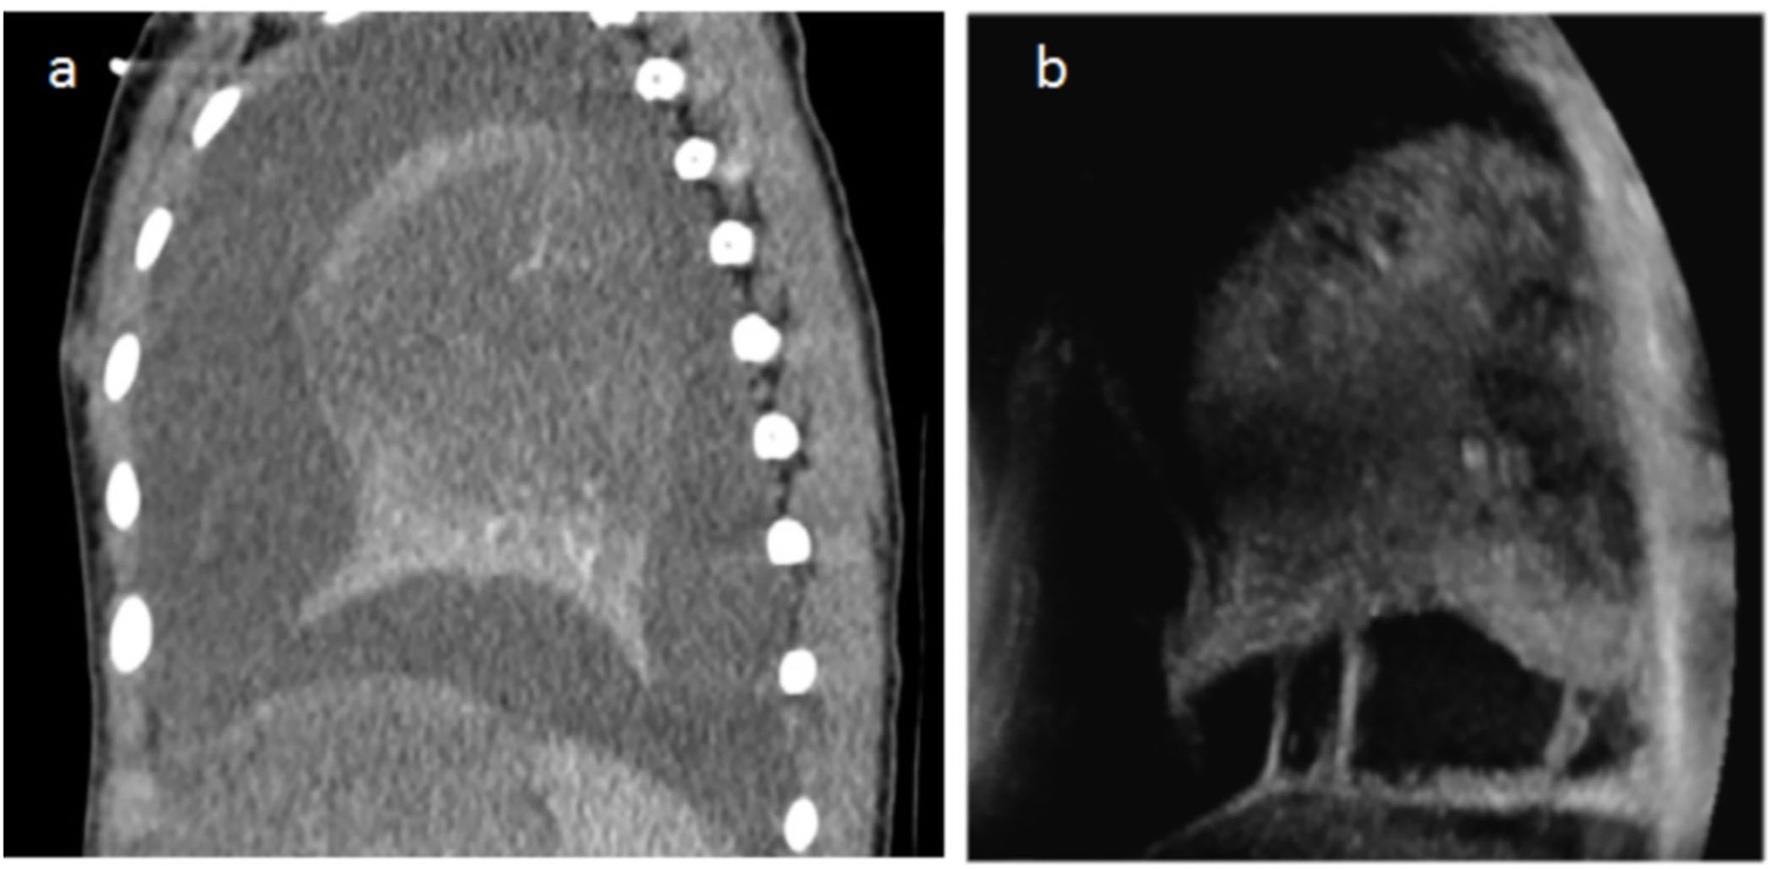

We found an excellent correlation between the two techniques in the evaluation of the pulmonary parenchymal disease—areas of consolidation and delimitation of necrosis (Figures 3, 4). As described in the statistics section, a comparison of the specificity and sensibility of the LUS with the gold standard (i.e., chest CT) for the detection of lung necrosis was not feasible because there were no false-positive LUS. LUS performed better than CT in identifying septations within the pleural effusions (Figure 3), whereas CT allowed a better visualization of (hydro-)aeric cavities and atelectasis.

Figure 3

(a) Chest CT with contrast agent injection in a 2.5-year-old child with 39°C fever, cough, and breathing difficulties. Sagittal reconstructions show a heterogeneous lung with unenhanced parenchyma corresponding to necrosis and a large pleural effusion. The US performed the same day also shows heterogeneity and hypodensity of the parenchyma in the necrotic zones (same as on CT) and pleural effusion. The periphery of the lower lobe is spared in a similar way on LUS and CT. In addition, US demonstrates bands of fibrin within the effusion, not visible on CT (b).